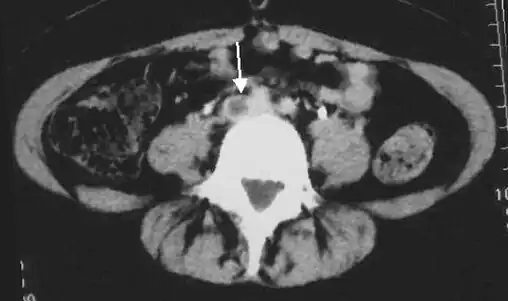

Doppler ultrasonography showing absence of flow and hyperechogenic content in a clotted femoral vein (labeled subsartorial[h]) distal to the branching point of the deep femoral vein. When compared to this clot, clots that instead obstruct the common femoral vein (proximal to this branching point) cause more severe effects due to impacting a significantly larger portion of the leg.[122] - An abdominal CT scan demonstrating an iliofemoral DVT, with the clot in the right common iliac vein of the pelvis